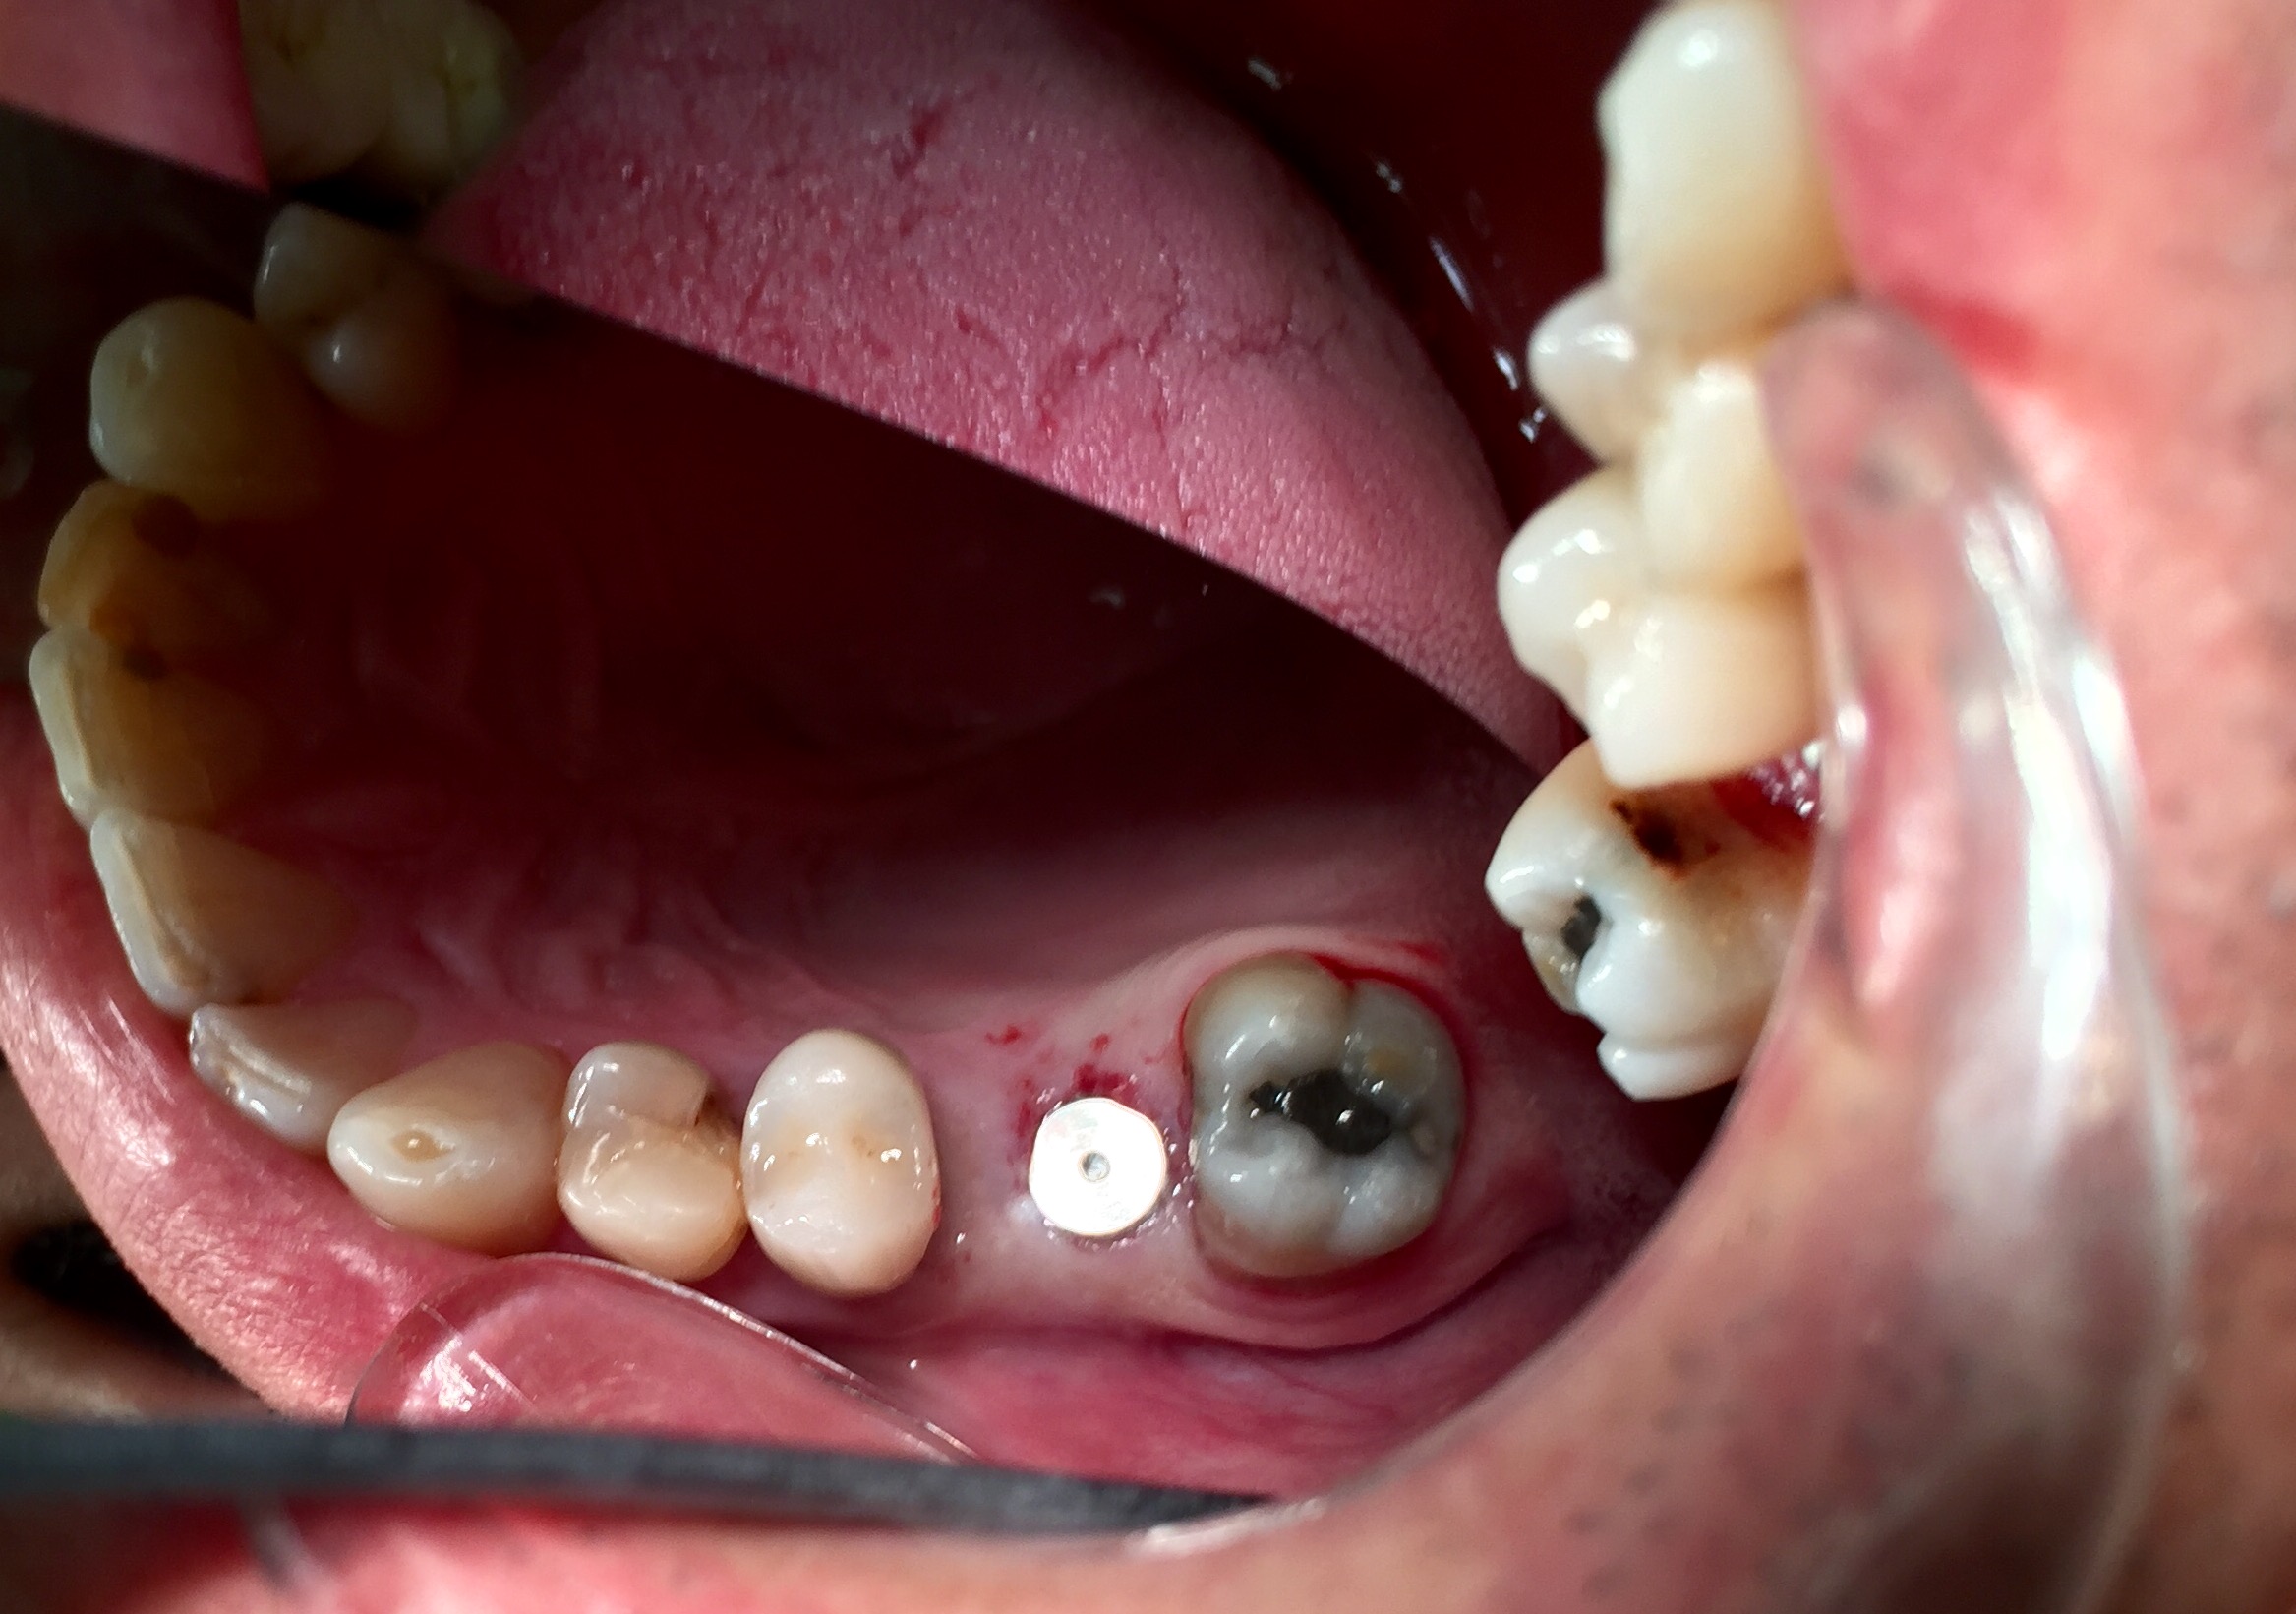

Consiste in un inserimento totalmente indolore previa anestesia locale di una "vite" appositamente studiate per il singolo caso.

La "vite" è filettata all'esterno e all'interno: esternamente per avere un'ottima presa sul tessuto osseo del processo alveolare superiore o inferiore, internamente per consentire il posizionamento della protesi definitiva che è l'unica parte visibile e ricalca quella che è l'anatomia dell'elemento sostituito.

Ogni intervento di implantologia viene preceduto da una diagnosi tramite Tc Cone Beam 3D di ultima generazione.